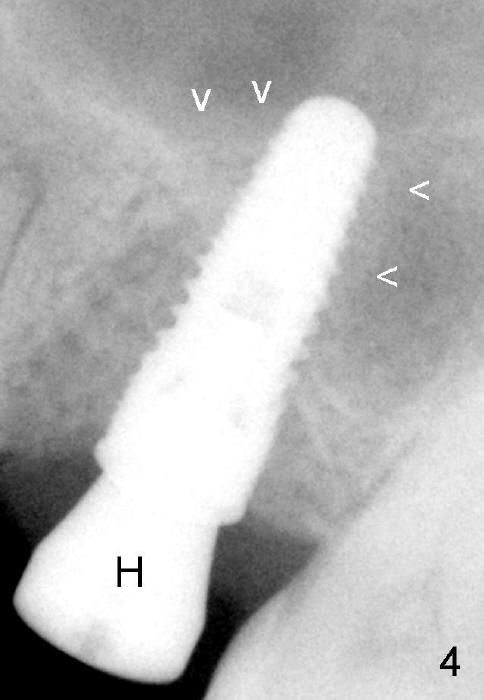

Fig.4 is taken 3.5 months postop. The amount of bone surrounding the apex of the implant is slightly reduced. As the implant starts to have function, the density may increase. H: healing abutment.